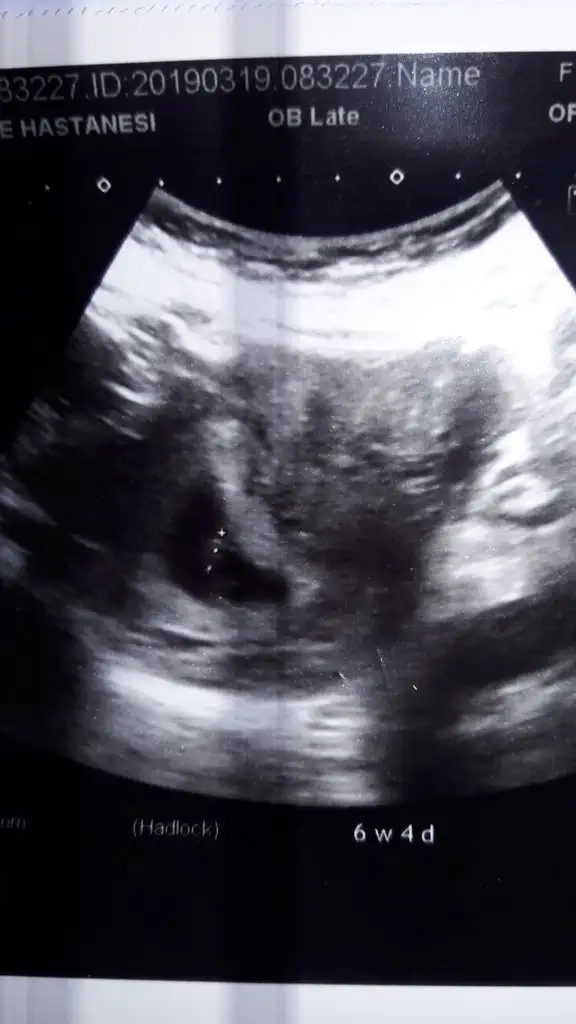

Merhaba kizlar normalde 7+4 olmam lazim ultrasonda 6+4 ciktim sizce konuma gore cinsiyti ne bana cok ortada geldi sanki karar veremedim